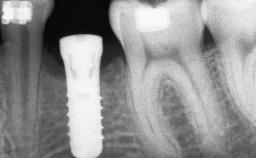

A woman in her mid-fifties was referred by a dental student for dental implant placement. Both posterior segments of the mandible had been edentulous for more than 4 years, the only residual tooth being the right lower first premolar. The patient had used a removable partial denture but was not entirely satisfied with its function. The clinical examination revealed a sharp edentulous ridge in both posterior segments of the mandible, and the patient was told that it would not be possible to insert implants into this thin edentulous ridge without significant augmentation of the alveolar ridge. Her medical history revealed no significant findings and no underlying disease that might have complicated surgical procedures. During the presurgical examination, the patient reported that she was a little apprehensive about bone grafting. After being informed about the surgical procedures and potential postoperative complications, she accepted the proposed surgical plan of bone grafting and subsequent placement of implants.

Bone Volume Deficient horizontally, requiring prior grafting